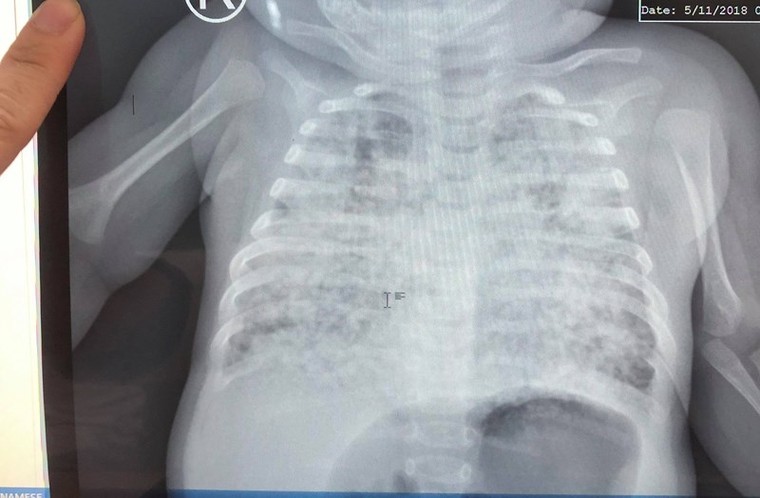

Sau 3 tháng, bé dần hồi phục - Ảnh: VTC News

Được theo dõi điều trị tích cực hơn 3 tháng, lệ thuộc oxy hơn 3 tháng tưởng chừng như không còn cơ hội sống, nhưng điều kỳ diệu đã đến với bé, phổi bé sáng dần lên, mô phổi giảm tổn thương và thông khí ngày càng hiệu quả, các kén khí lớn giảm rõ rệt.